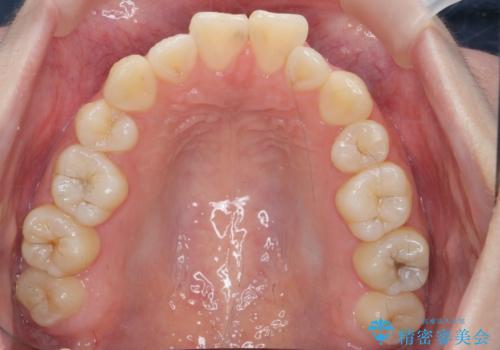

- 前歯の角度 奥歯の噛み合わせの改善をするために、矯正治療を希望され来院されました。

右側奥歯は上顎が相対的に前方に位置し(上顎前突)、そのため前歯の角度も突き出たようになり出っ歯のように見える状態でした。

マイクロインプラントを用いて、上顎奥歯を後方に移動させることで噛み合わせ・前歯の角度を改善していきます。

少し時間はかかりましたが、しっかりと綺麗な歯並びに仕上げることができ、大変喜んでいただくことができました。